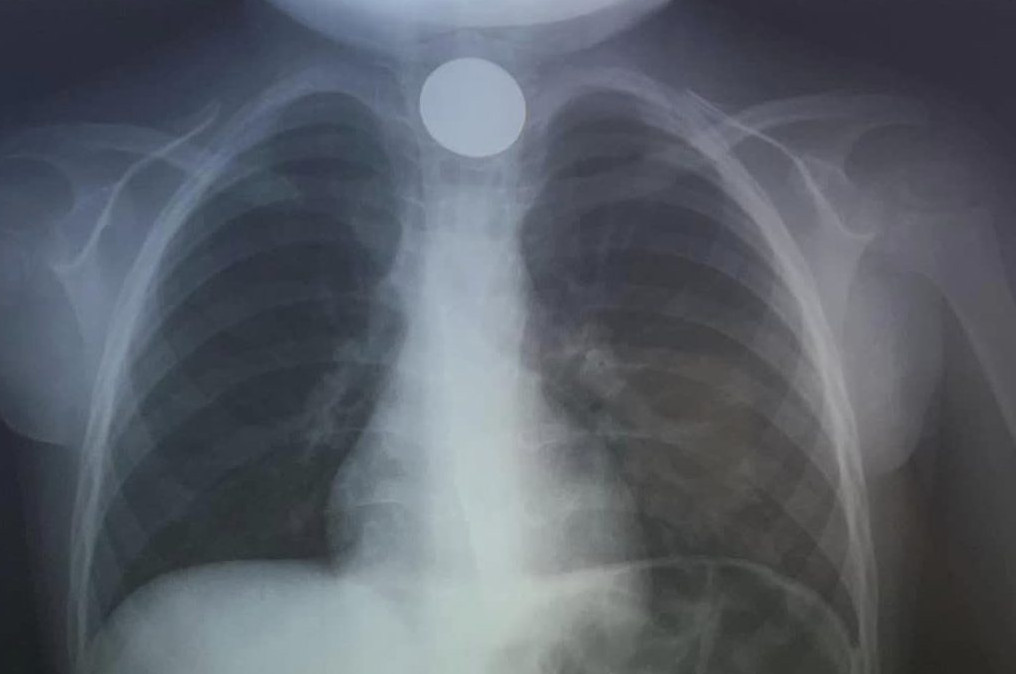

Όταν έφτασαν στο ΠΑΓΝΗ, η πρώτη κίνηση των γιατρών ήταν να του κάνουν ακτινογραφία, για να δουν σε ποιο σημείο ακριβώς είχε σταθεί το νόμισμα και αμέσως μετά προχώρησαν στη διαδικασία αφαίρεσής του. Δεν πέρασε πολύς χρόνος και οι γιατροί ακτάφεραν να αντιμετωπίσουν επιτυχώς το επείγον περιστατικό, λύνοντας ταχύτατα το πρόβλημα.